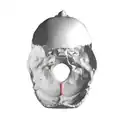

Base of the skull. Internal occipital crest shown in red.

Base of the skull. Internal occipital crest shown in red. -